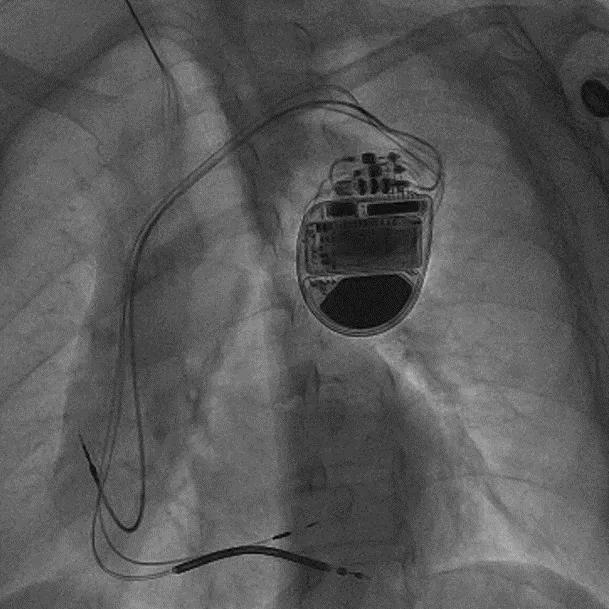

拔除无导线起搏器后植入左束支CRTD的术后影像

治疗团队经过充分讨论并评估了手术风险及预后,与家属反复沟通,决定为张女士实施无导线起搏器移除+生理性起搏+心脏再同步除颤器(LOT-CRTD)植入术。术前,汤宝鹏教授带领治疗团队进行了详细的文献查阅和充分的病情评估,对术中可能出现的各种风险做好了应急预案。术中,手术团队使用圈套器成功抓捕无导线起搏器Micra尾端并顺利拔除,同时给患者植入左束支心脏再同步起搏除颤器。手术顺利,患者术后恢复良好。